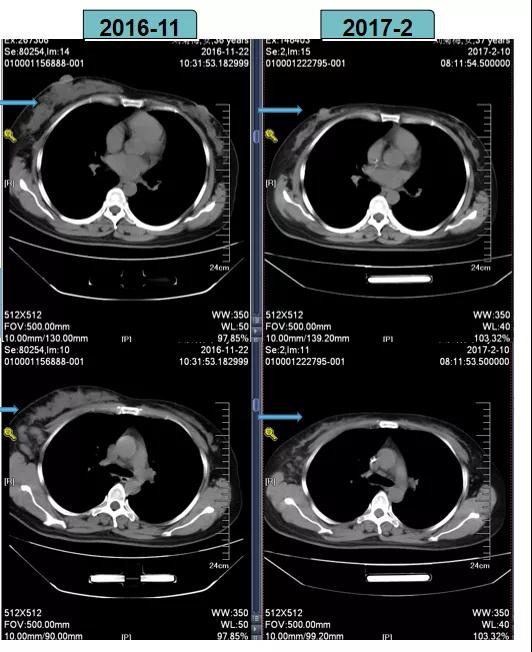

根据当时CSCO BC指南推荐的HER2阳性乳腺癌新辅助治疗策略,2016-11-29至2017-1-16给予TCbH方案进行新辅助化疗,后疗效评估为PR。

具体方案:曲妥珠单抗8mg/kg负荷剂量,6mg/kg维持剂量 d1;脂质体紫杉醇300mg 静滴d2;卡铂 600mg 静滴 d2 q3w*3。

TCbH方案进行新辅助化疗后,患者疗效评估为PR

2017-2-10全麻下行右乳癌改良根治术。

术后病理(B201703357):病灶体积2cm×2cm×2.8cm,“右侧”乳腺非特殊型浸润性导管癌Ⅲ级,“右侧”腋窝淋巴结(18/18个)有癌转移。

免疫组化:ER(-),PR(-),HER2(3+),Ki-67(+40%)

术后诊断:右乳浸润性导管癌(ypT2N3aM0,IIIC期)。